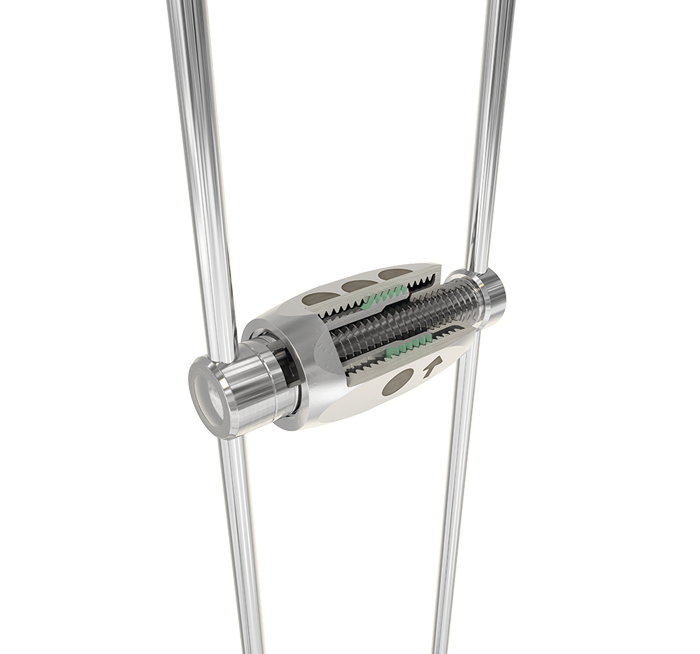

PowerScrew Tiger Dental este un șurub mecanic de expansiune, utilizat în realizarea aparatelor ortodontice și a sistemelor ce necesită deplasarea controlată. Dispune de mecanism filetat de precizie, care permite activarea graduală și distribuția uniformă a forței. Construcția robustă asigură stabilitate și rezistență în utilizare.

Dimensiuni disponibile: 8 mm, 10 mm, 12 mm, 14 mm